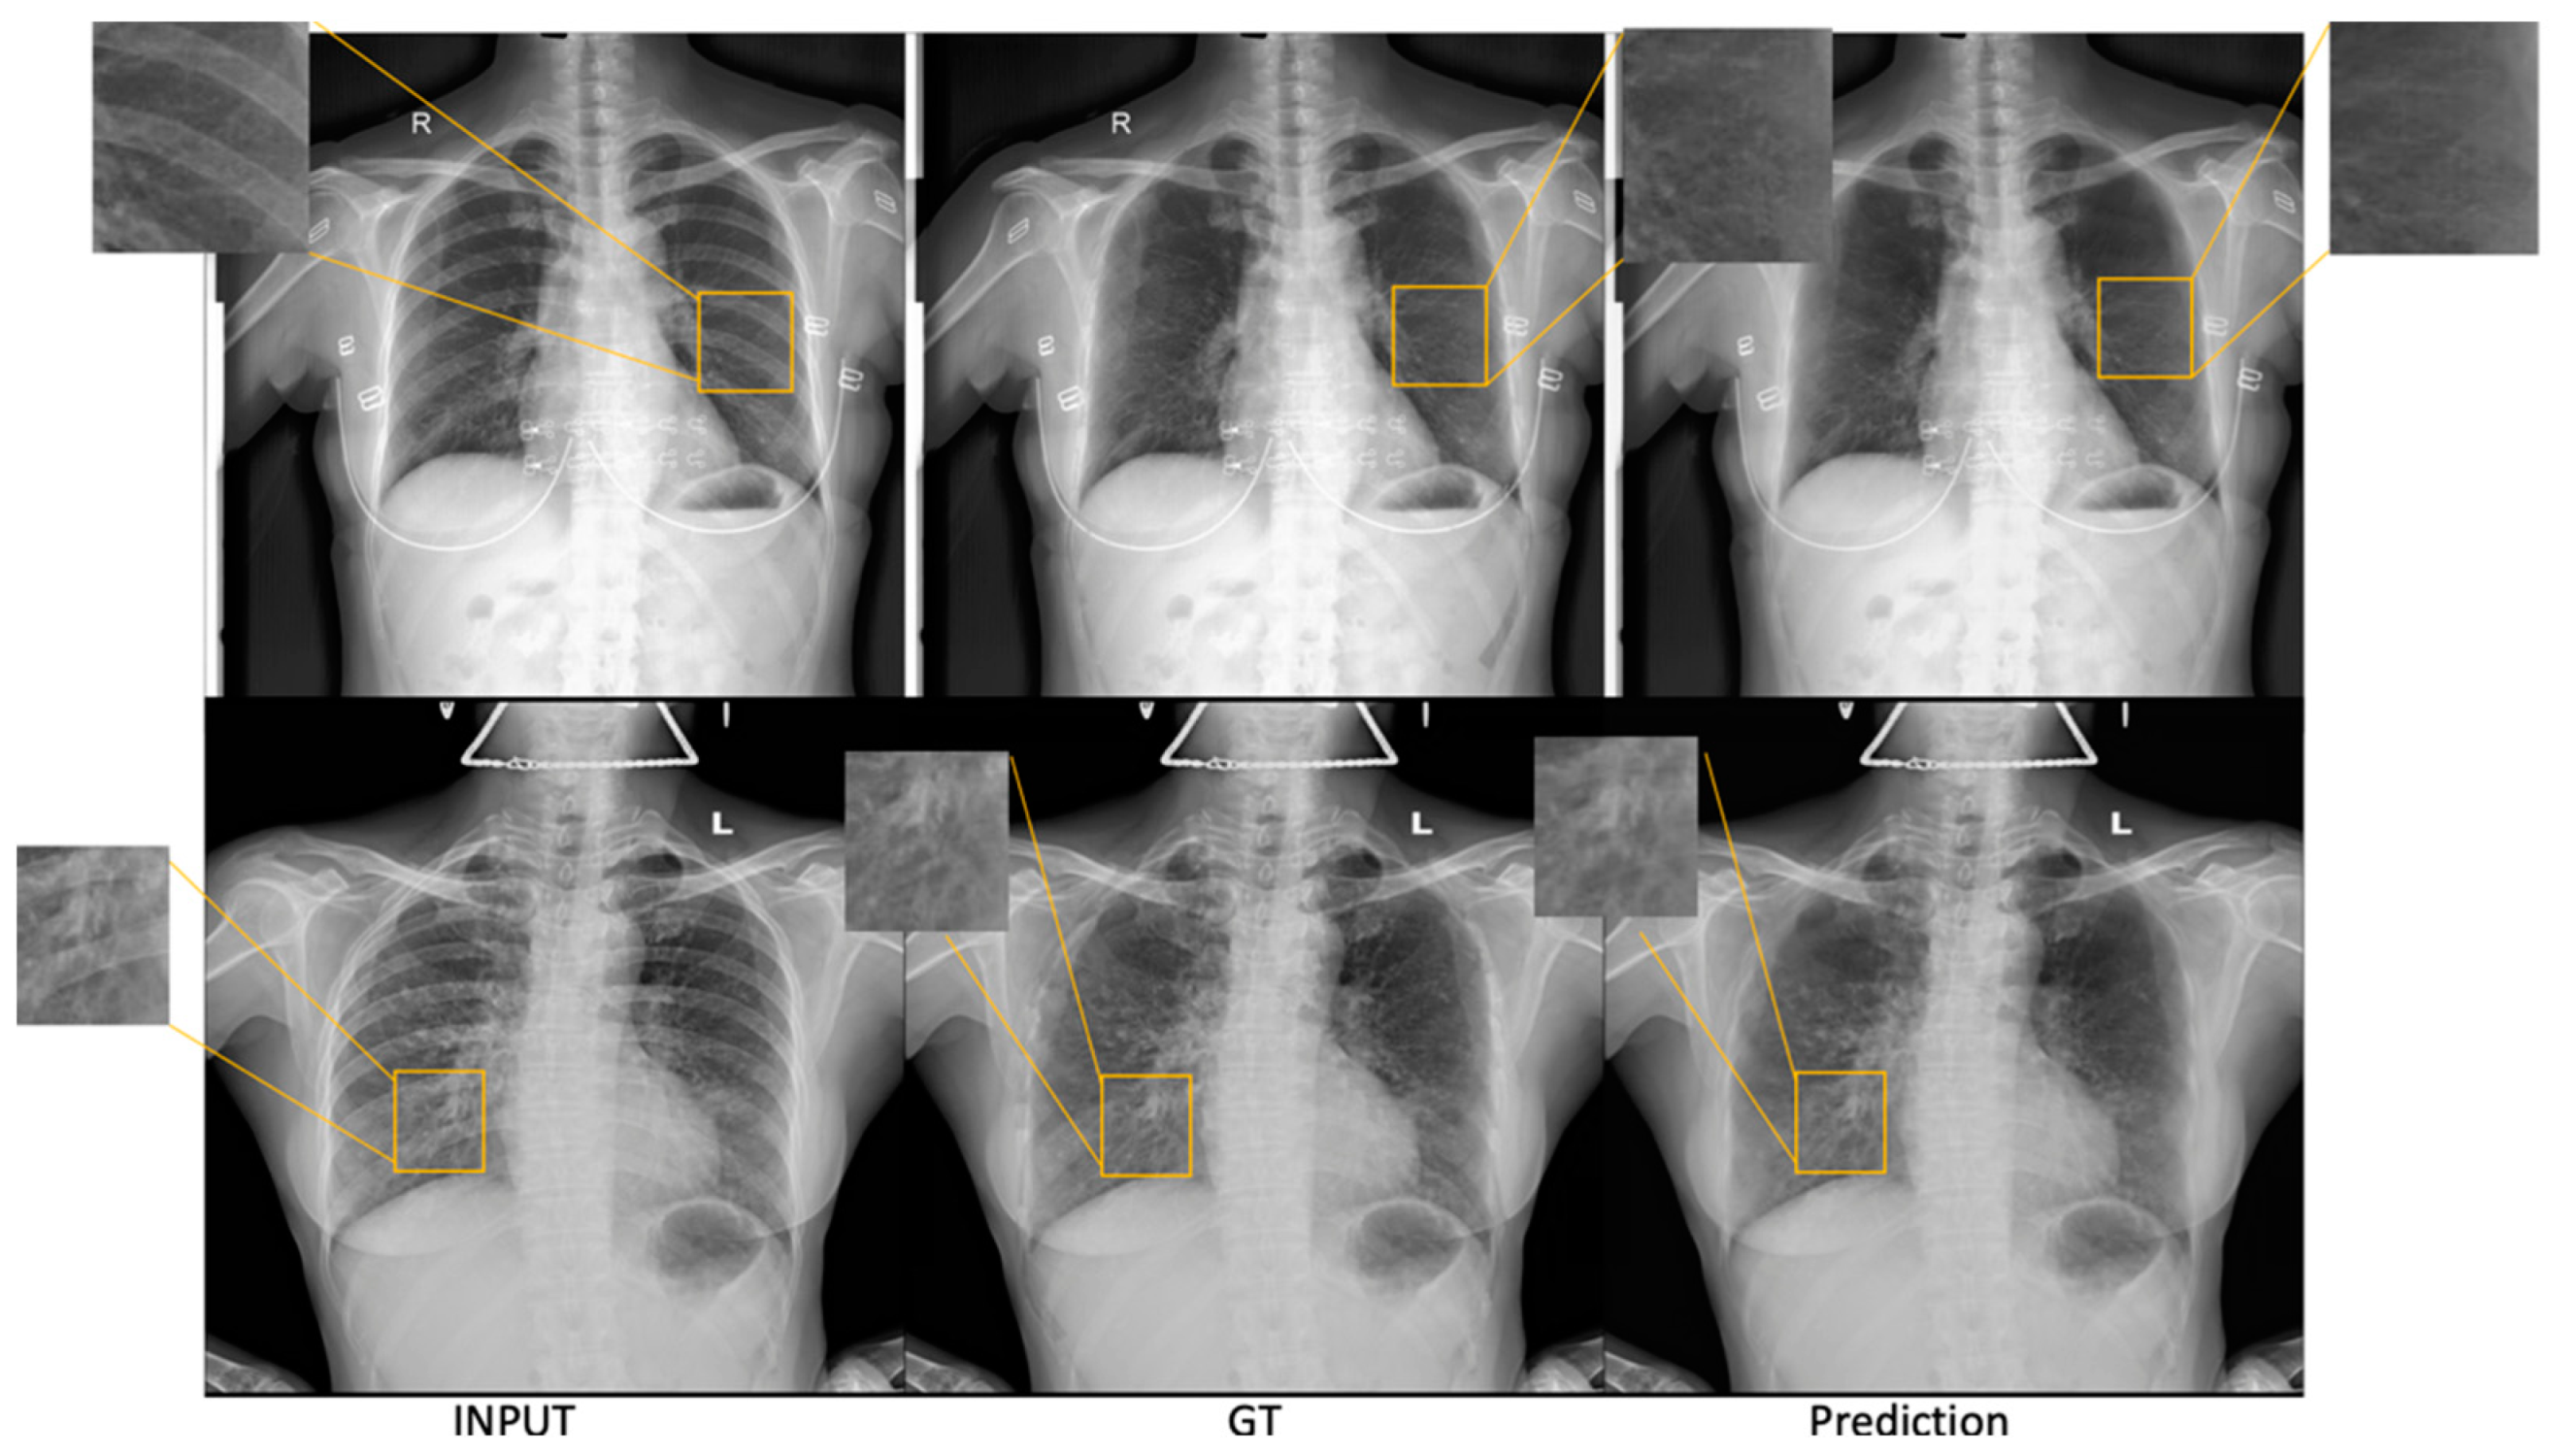

3.1.1. ST Smoothing

3.1.2. SADXNet